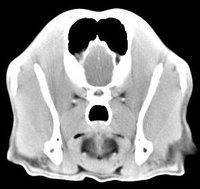

Diagnóstico neurológico | ||||||||||

imágenes de TC en el perro | ||||||||||

ejemplo de imágenes de TC en el perro. Nótese la celulitis en la región parotídea izquierda | ||||||||||